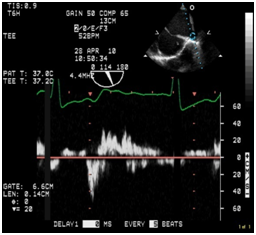

After emptying the stomach, the TEE probe was placed without difficulty. IABP was placed via the right femoral artery. Position of the IABP was confirmed with the TEE. Operation of the IABP was confirmed. A left femoral venous cordis was placed and central access was established. Preoperative TEE found an LV ejection fraction of approximately 5%, severely dilated LV (Figure 1a & Figure 1b), moderately dilated right ventricle, and moderate to severe right ventricular hypokinesis. Patient had a 4+ MR, with significant reversal of the systolic component of the right superior pulmonary venous profile (Figures 1c & Figure 1d).

Figure 1d Pulsed wave Doppler of the right superior pulmonary vein demonstrating reversal of the systolic component of the pulmonary venous profile. Consistent with the severe MR.